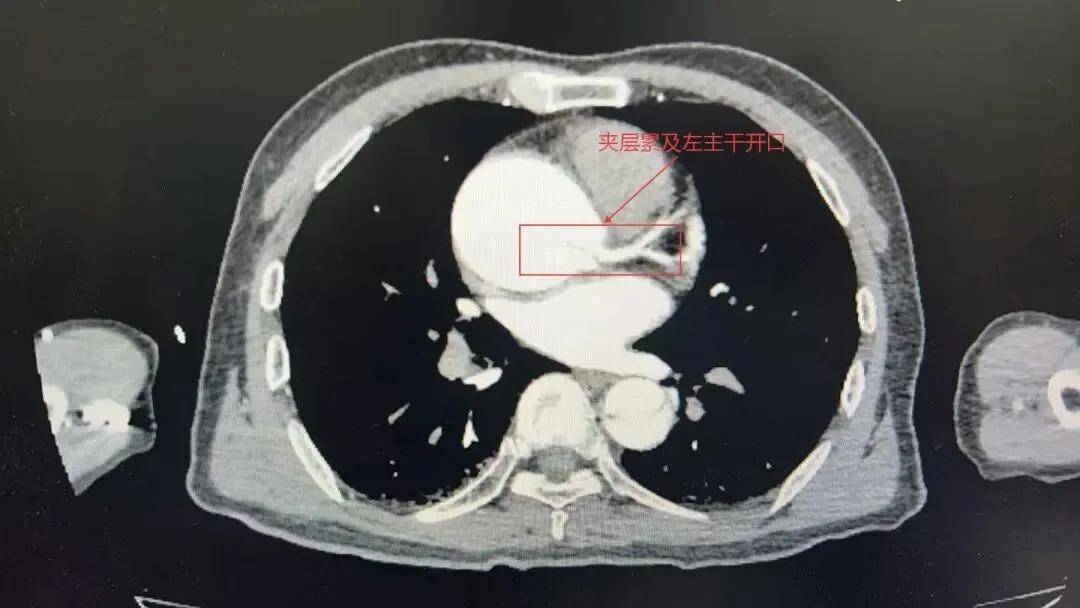

当晚紧急转入河南省胸科医院后,张力复查影像,发现患者夹层已累及左主干,血管随时可能破裂,属于极高危风险。